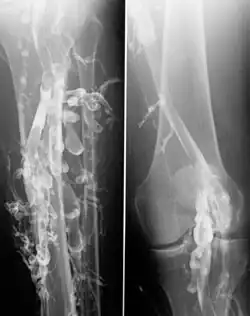

Venography in a patient with deep vein thrombosis

Contrast venography is the gold standard for judging diagnostic imaging methods for deep vein thrombosis; although, because of its cost, invasiveness, and other limitations, this test is rarely performed.[1]